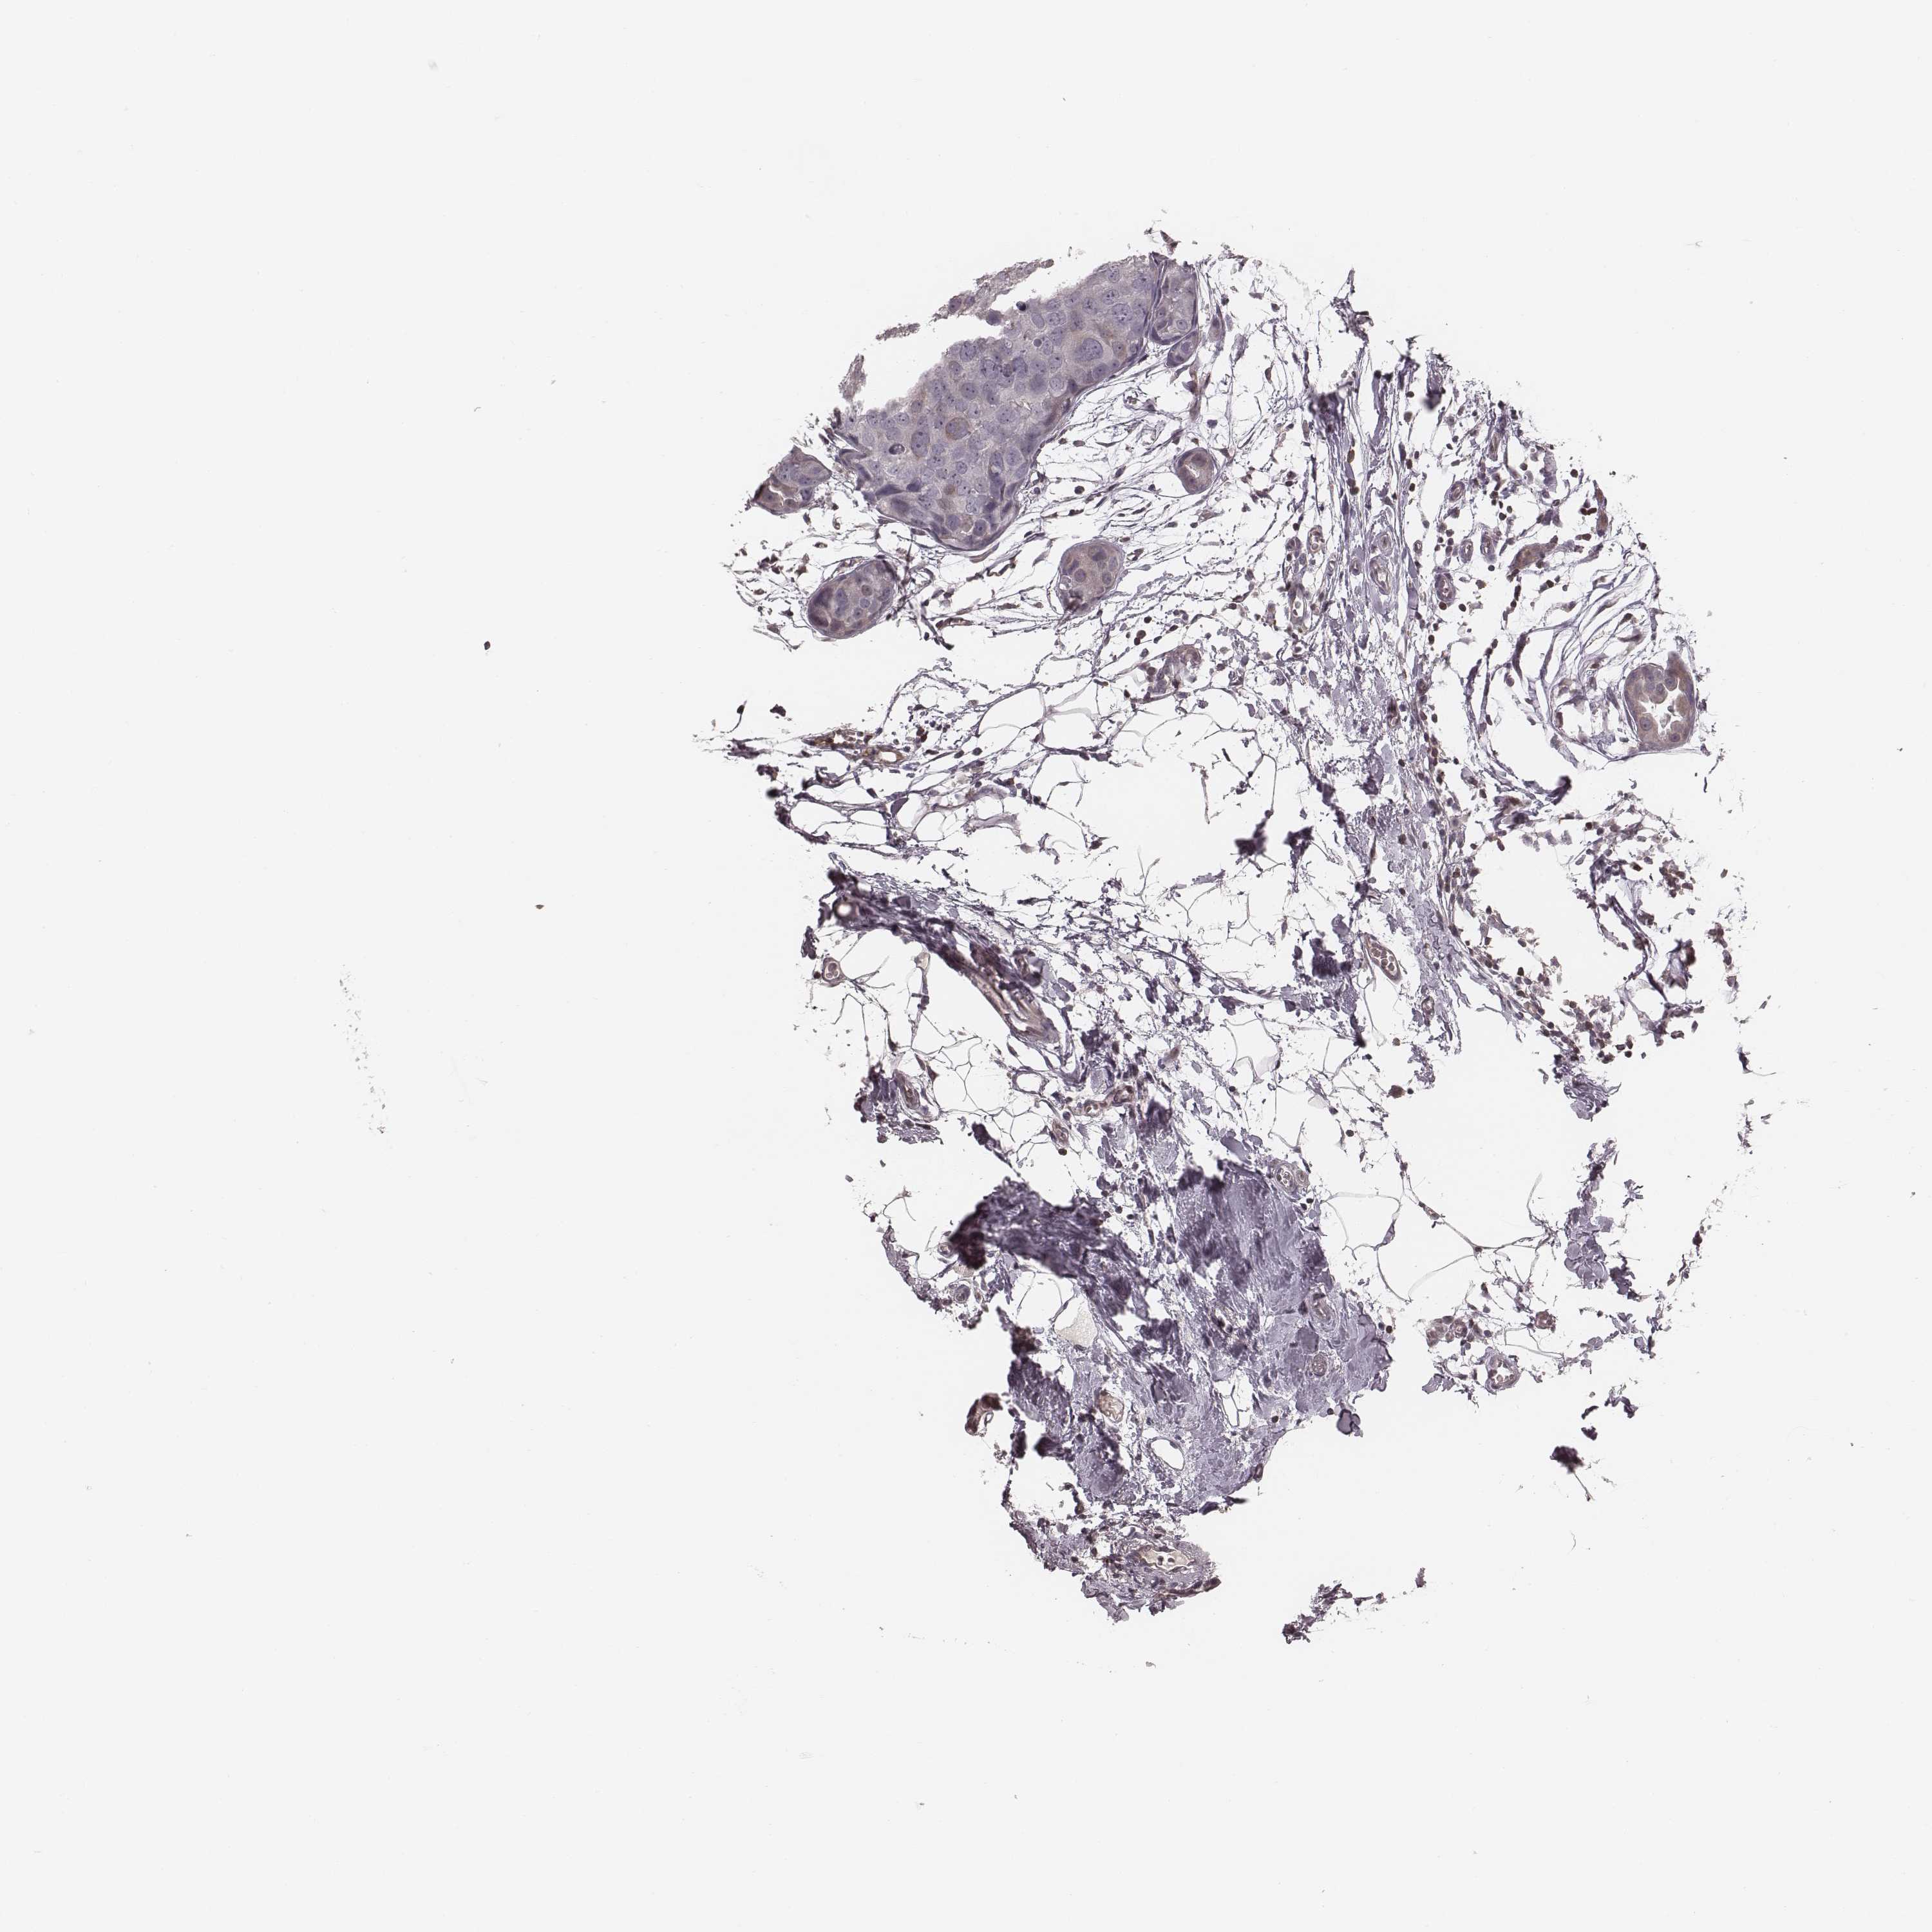

BRCA TCGA BRCA VALIDATION PROTEIN EXPRESSION

ANTIBODIES

AND

VALIDATION